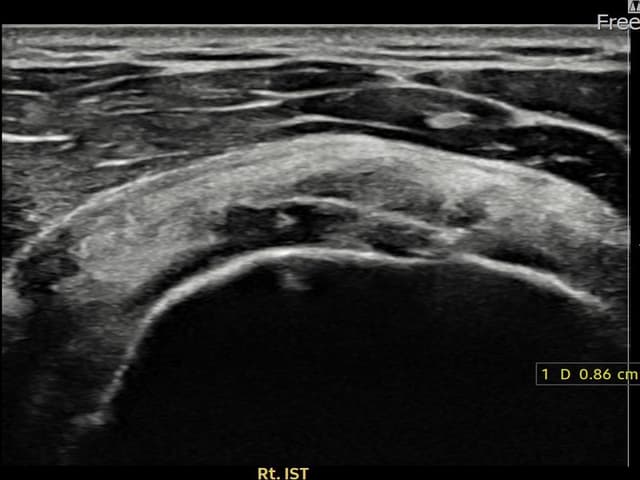

右侧 冈下肌腱 附着部部分撕裂

8.6mm × 4mm (肌腱厚度约45%缺损)